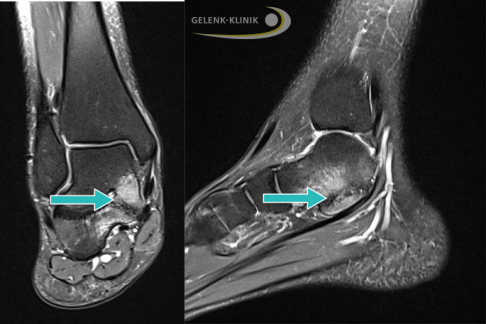

MRT eines Jugendlichen mit Koalition zwischen Fersenbein und Kahnbein (Coalitio calcaneonavicularis, Pfeil). Knochenstrukturen erscheinen im MRT dunkel. Die sichtbaren weißen, knöchernen Veränderungen sind mit einer vermehrten Flüssigkeitsansammlung gleichzusetzen (Knochenödem) und deuten auf eine Reizung des Knochens hin. © Gelenk-Klinik